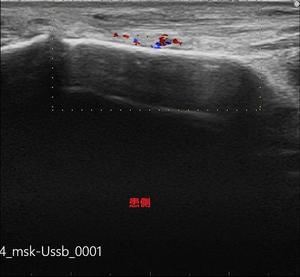

今回はエコー検査を行い、まだ疲労骨折にはいたっていないですが、

このまま無理に動いていると、必ず疲労骨折を発症する為、安静・治療となりました。

中足骨骨膜炎-患側.jpg